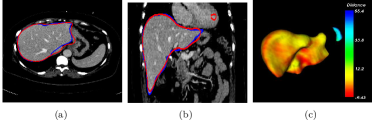

Refer to caption

Figure 5: Illustrations of the segmentation results by the proposed method. The contour of the segmentation result is in red with ground truth in blue. a 2D view in axial plane, b 2D view in coronal plane, c the surface distance error (mm) of the proposed with the ground truth

From the initial liver shape L0subscript𝐿0L_{0}, the intensity range for liver can be roughly estimated as [ζ,η]=[m3σ,m+3.5σ]𝜁𝜂𝑚3𝜎𝑚3.5𝜎[\zeta,\eta]=[m-3\sigma,m+3.5\sigma], where m𝑚m, and σ𝜎\sigma are the intensity mean and variance over L0subscript𝐿0L_{0}, respectively. In the practical usage, parameters used in graph cut are chosen as follows. The balancing weight λ=70𝜆70\lambda=70, γ=i=13σ02/36𝛾superscriptsubscript𝑖13superscriptsubscript𝜎0236\gamma=\sum_{i=1}^{3}{{\sigma_{0}}^{2}}/36, β=0.2𝛽0.2\beta=0.2; the local window O(x)𝑂𝑥O(x) is chosen as a cube window of 9×9×59959\times 9\times 5 and the LBP parameters are chosen as τ=1.5𝜏1.5\tau=1.5, P=6𝑃6P=6, r=1𝑟1r=1. The graph cut segmentation is implemented with C++ on a desktop computer with an Intel Core i5-4460U CPU (3.20 GHz) and a 8 GB of memory. Fig. 5 shows the final segmentation of the case as shown in Fig. 4. For a test volume with size of 512×512×n512512𝑛512\times 512\times n (n<286)𝑛286(n<286),generating the liver likelihood map by 3D CNNs usually consumes about 4s and the graph cut segmentation varies from 20s to 180s.